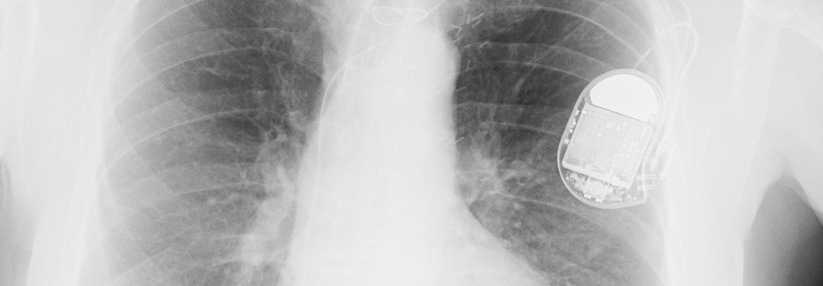

Auch das Patientenalter spielt eine erhebliche Rolle, wenn es um den Erfolg implantierter Defibrillatoren geht. Auch das Patientenalter spielt eine erhebliche Rolle, wenn es um den Erfolg implantierter Defibrillatoren geht. © iStock.com/Jan-Otto